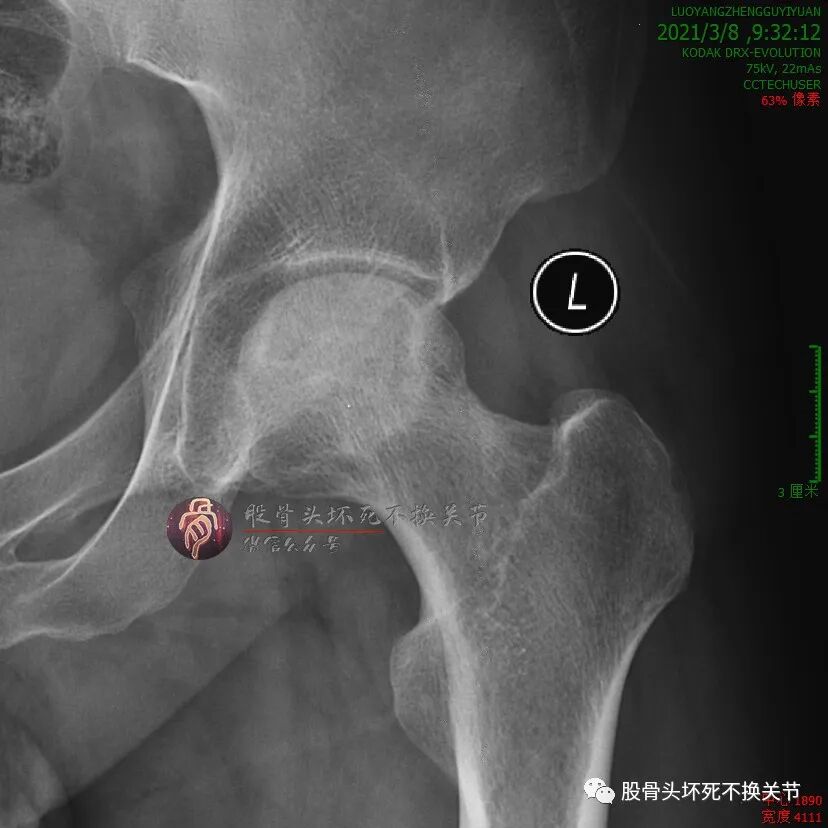

继续定期门诊治疗,又过了5个月:

还行吧,骨密度就那样。